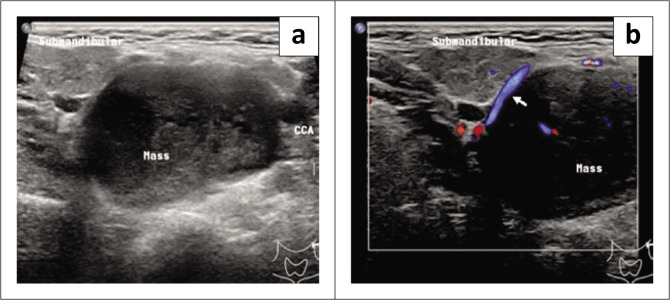

Nerve sheath tumours of the sympathetic chain are extremely rare and present a diagnostic challenge. A 42-year-old female presented with asymptomatic left cervical swelling. Imaging with sonography, CT, MR and angiography demonstrated a lesion splaying the carotid bifurcation, the lyre sign. Following surgical excision, histology revealed a schwannoma. Imaging features of carotid body tumours and parapharyngeal schwannomas can be similar, as both can cause splaying of the carotid bifurcation. The differential diagnosis of such tumours and their management are discussed.

Contribution: This article highlights another cause of the lyre sign on radiological imaging besides carotid body tumours.